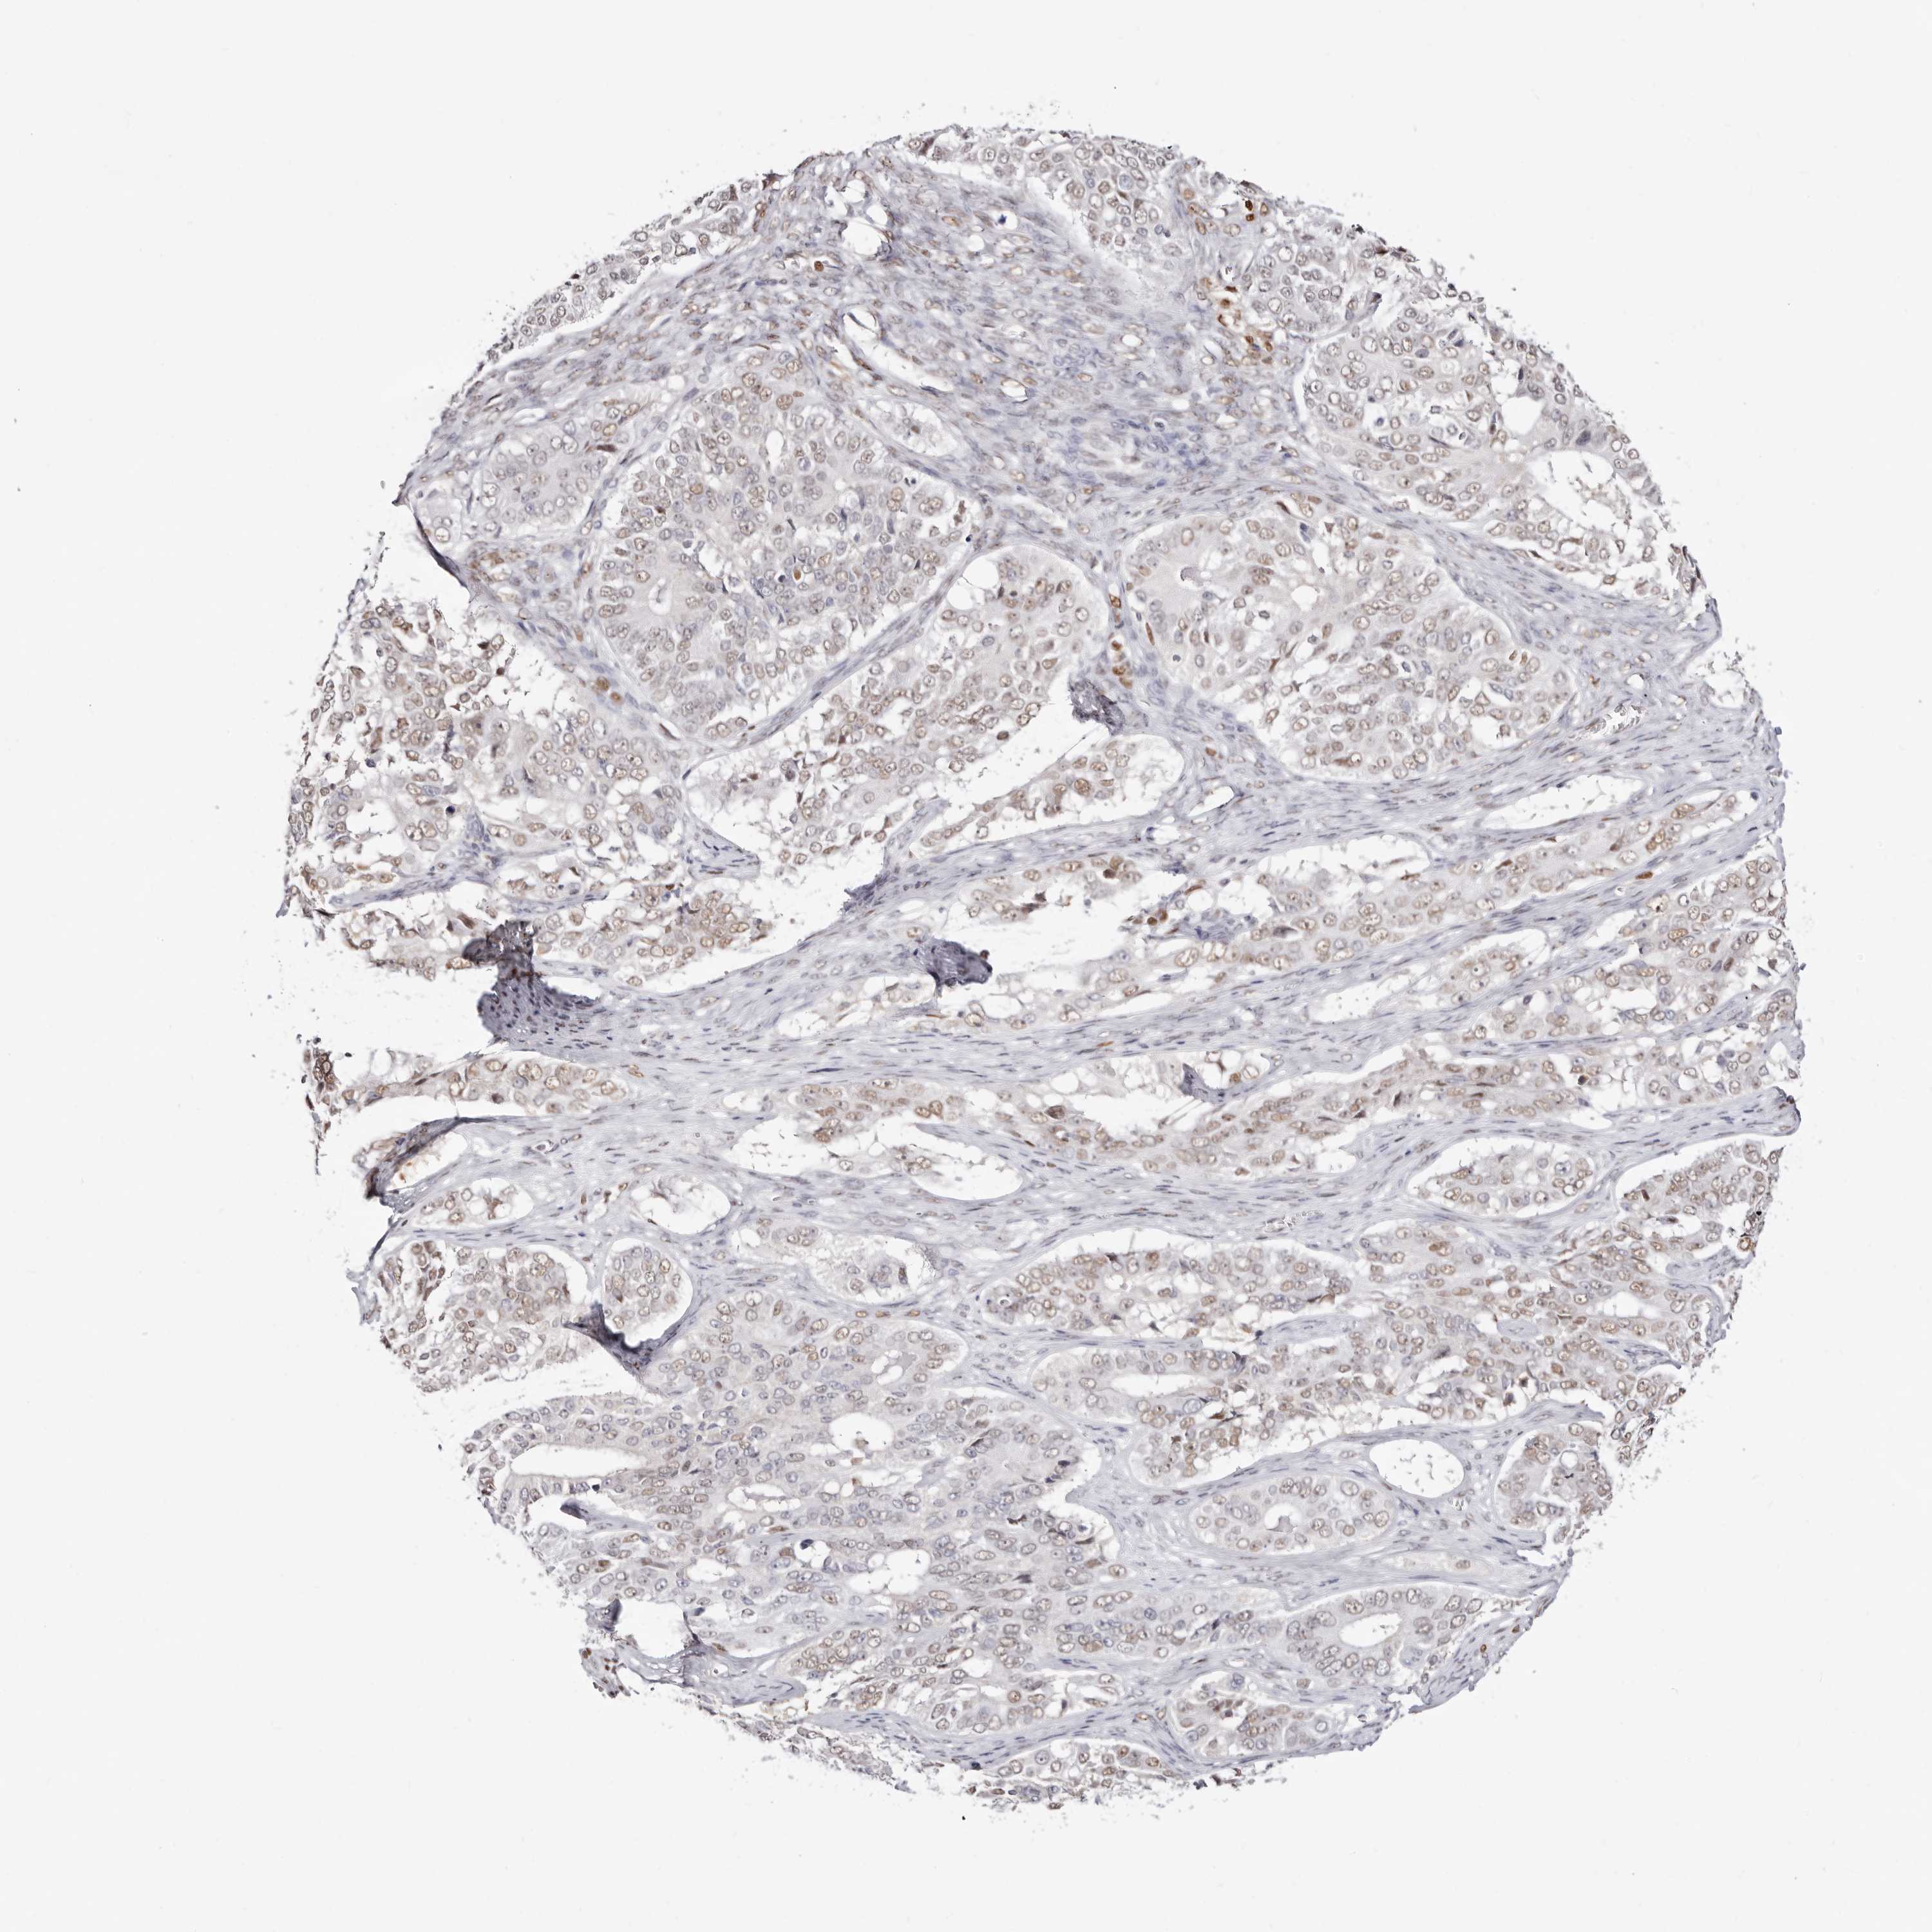

OVARIAN CANCER - Protein expressioni

A mouse-over function shows sample information and annotation data. Click on an image to view it in a full screen mode. Samples can be filtered based on level of antibody staining by selecting one or several of the following categories: high, medium, low and not detected. The assay and annotation is described here.

Note that samples used for immunohistochemistry by the Human Protein Atlas do not correspond to samples in the TCGA dataset.

Antibody stainingi

Antibody staining in the annotated cell types in the current human tissue is reported as not detected, low, medium, or high, based on conventional immunohistochemistry profiling in selected tissues. This score is based on the combination of the staining intensity and fraction of stained cells.

Each image is clickable and will lead to virtual microscopy that enables deeper exploration of all samples and also displays staining intensity scores, fraction scores and subcellular localization as well as patient and tissue information for each sample.

Antibody HPA029480

Antibody HPA029481

Cystadenocarcinoma, mucinous, NOS